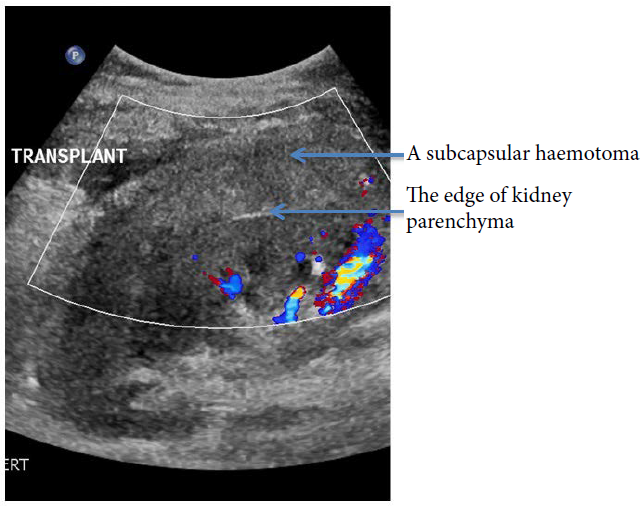

Figure 4: A subcapsular haematoma on Ultrasound.